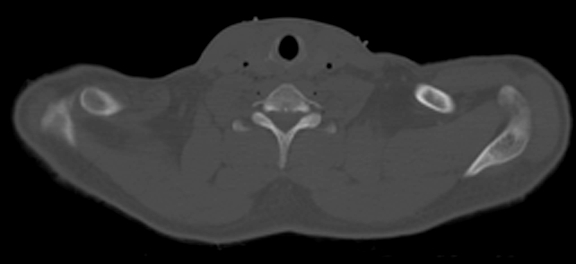

• Horizontal CT Section at this level